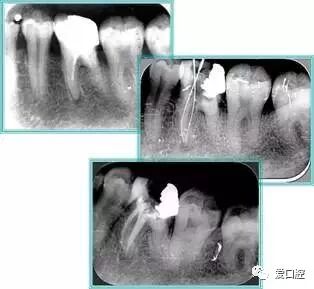

2. X 线片

共有 4 张 X 线片,分别是术前、诊断丝 、主牙胶尖确认、术后。

( 1 )术前:术前 X 线片用来了解牙齿的大概情况。术前预期为多根牙时 X 线片应偏头拍摄。

( 2 )诊断丝:根据术前 X 线片进行开髓、根管的初步预备后,需要插入诊断丝,用来指示工作器械位置。常用 10 号或 15 号扩大器作为诊断丝插入牙髓腔。

( 3 )主牙胶尖确认:通过术前预期和诊断丝诊断,明确工作长度、牙根走向,进行根管预备。之后应进行主牙胶尖(中锉)确认,已明确根管是否适合充填。

( 4 )术后:观察治疗效果。